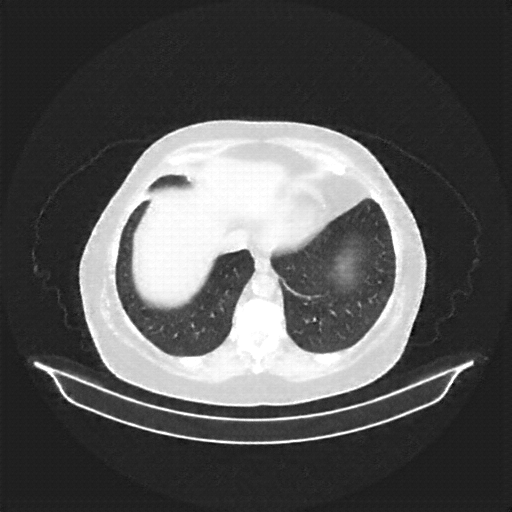

Original VENOUS CT scan

Mediastinum window (WL 40, WW 400 β†’ Low βˆ’160, High +240)

Generated VENOUS CT scan (A→B translation)

Full window (WL 1023.5, WW 4095 β†’ Low βˆ’1024, High +3071)